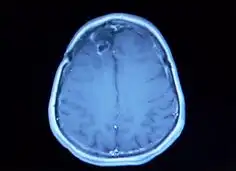

교모세포종의 진단은 주로 고해상도의 영상 진단 도구인 MRI 또는 CT를 통해 이루어집니다.

이러한 검사를 통해 종양의 위치, 크기 및 주변 조직과의 관계를 정확히 평가할 수 있습니다.

또한, 최종적인 진단을 위해서는 조직 검사가 필수적으로 수행됩니다.